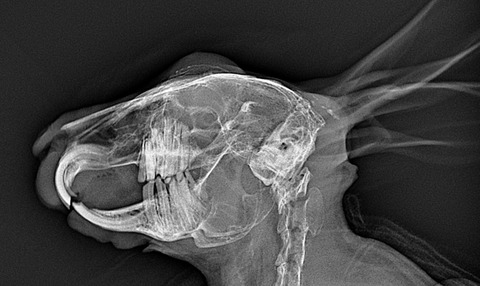

では歯並びが歪んでるとはどういうことかを、レントゲン画像でご紹介します

⇩これが不揃いの子だと

歯根が揃ってないのがわかるかと思います、こういう歯根の子では現状問題なくても膿瘍の発生が警戒されます

健康診断時には歯のレントゲンを撮ってもらっても良いのかもしれませんね

横向けにウサギを寝かせて上からX線を照射し撮影しているので、左右の歯が重なってしまい完璧な評価ができる訳ではないですが、参考にはなります

(理想的にはCTで全ての歯根をチェックするのが望ましい)

歯根の炎症が慢性化すると、歯も変性して濃い白で写ってくるようになります